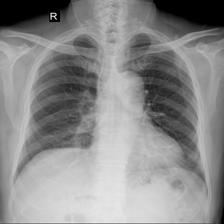

To pre-train a high-performance X-ray foundation model, the first thing we need to do is the collection of large-scale X-ray images. Therefore, a large-scale and high-resolution dataset that contains X-ray medical images is collected for the pre-training. Some representative samples are visualized in Fig. 3.

As shown in Fig. 8, we provide some representative samples predicted by our model. The and column are the raw X-ray images, the and column are masked images, and the and column are the reconstructed images. We can find that our proposed context-aware masking strategy guided MAE framework predict the masked tokens well.

As shown in Fig. 9, given the text lungs, we can find that the activation maps can accurately highlight the target regions. Therefore, we can achieve a higher performance on the downstream tasks. However, the activation maps are imperfect, as the background regions are also highlighted.